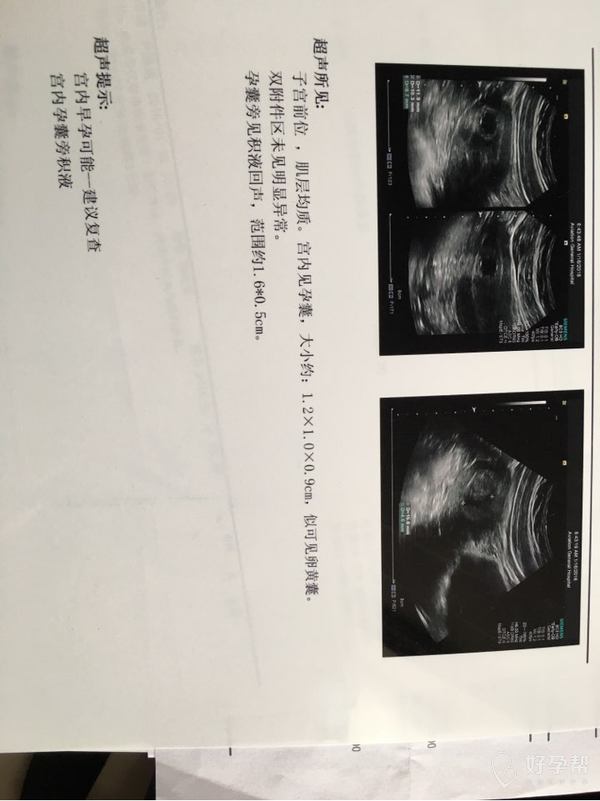

医生帮忙看看,末次月经11.26号,医生说胚胎发育不好,而且hcg隔天翻倍不乐观,目前只有15000,现在我是等着复查还是需要做手术呢,心情很乱[流泪][流泪],麻烦医生帮帮忙,给个好的意见